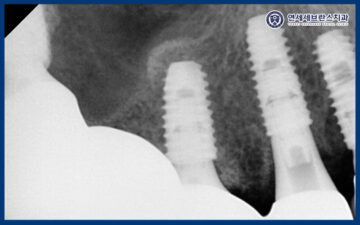

아울러 위쪽 큰 어금니 부위는

잇몸뼈의 두께가 얇아 임플란트를

바로 식립하기 어려운 상태였기 때문에,

상악동거상술을 시행하여

충분한 뼈이식을 진행한 후

임플란트를 식립하기로 하였습니다.

오른쪽 위 첫 번째 큰 어금니 부위는

앞서 말씀드린 것처럼

잇몸뼈의 양이 충분하지 않은 상태였기 때문에,

상악동 측방 거상술을 통해

부족한 뼈를 보강한 후

임플란트를 식립하였습니다.

상악동거상술을 통해

임플란트가 안정적으로

자리 잡을 수 있는 충분한 공간을 확보하고,

장기적인 예후를 고려한

치료를 진행하였습니다.